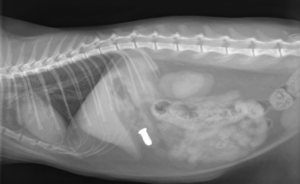

Kat die een schroef heeft ingeslikt -deze bevindt zich op de röntgenfoto in de maag, omdat het risico te groot werd ingeschat dat het vast zou kunnen lopen in een darm is tijdens een endoscopie de schroef verwijderd.

Schroef in de maag van een kat. Deze is succesvol verwijderd door middel van een endoscopie op het MCD.